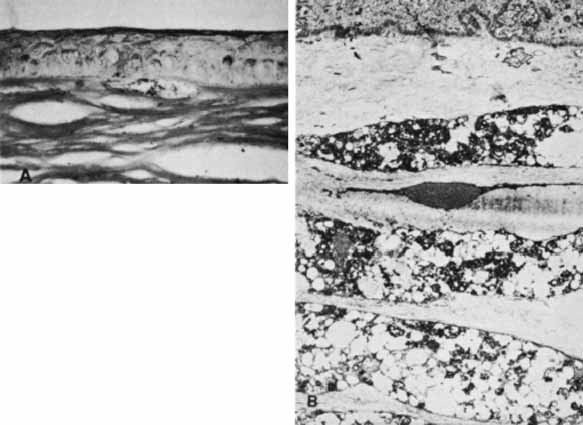

All patients with MPS and mucolipidoses in which corneal histopathology has been studied have demonstrated abnormal deposition of storage substrate, even in cases in which they were not clinically evident (Table 4). The hallmark histopathologic findings in these disorders are storage of excess glycosaminoglycan and glycolipid as membrane-bound vacuoles in keratocytes (Fig. 12). The glycosaminoglycans stain blue with colloidal iron and Alcian blue, and the glycolipids are best seen in frozen sections of unfixed tissue. Transmission electron microscopy demonstrates single membrane-bound cytoplasmic vacuoles containing fine fibrillogranular material along with lamellar bodies, likely representing glycosaminoglycans and glycolipids, respectively. These vacuoles can distend the keratocyte to many times their normal size, making them clinically visible as fine punctuate opacities. In more advanced cases, a fine extracellular granular material surrounds the keratocyte and contributes to the gray stromal haze seen clinically.

Fig. 12 Cornea showing subepithelial accumulation of glycosaminoglycan (colloidal iron, ×400). B. Cornea from MPS-VI micrograph shows fibrillogranular material in the cytoplasm of keratocytes (×6000). (courtesy of K. Kenyon, MD)

There are also disorders for which the corneal opacity is not a result of keratocyte involvement.90 In Fabry's disease, although there is some keratocyte involvement, it is postulated that the corneal opacity results primarily from sphingolipid deposition in the epithelial cell layer.94 In mucolipidosis IV, a majority of lipid deposition also occurs in the epithelial layer with relative sparing of the keratocytes.90 In cases with epithelial involvement, the epithelial cells become distended and disrupted like the keratocytes, and in more advanced cases fibrous proliferation occurs at the level of Bowman's layer.